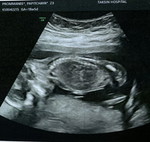

กำหนดคลอดน้อง 3ก.พ65 ตอนนี้33week เราควรลางานช่วงไหนค่ะ